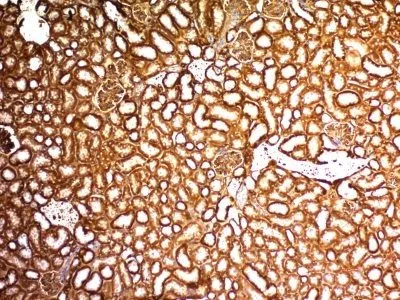

Recognizes a 47-55 kDa-tumor suppressor protein, identified as Wilm's Tumor (WT1) protein. The antibody reacts with all isoforms of the full-length WT1 and also identifies WT1 lacking exon 2-encoded amino acids, frequently found in subsets of sporadic Wilm s tumors.WT1, a sporadic and familial pediatric kidney tumor, is genetically heterogeneous. Wilm s tumor is associated with mutations of WT1, a zinc-finger transcription factor that is essential for the development of the metanephric kidney and the urogenital system. The WT1 gene is normally expressed in fetal kidney and mesothelium, and its expression has been suggested as a marker for Wilm s tumor and mesothelioma. WT1 protein has been identified in proliferative mesothelial cells, malignant mesothelioma, ovarian carcinoma, gonadoblastoma, nephroblastoma, and desmoplastic small round cell tumor. Lung adenocarcinomas rarely stain positive with this antibody. WT1 protein expression in mesothelial cells has become a reliable marker for the diagnosis of mesotheliomas.Primary antibodies are available purified, or with a selection of fluorescent CF® Dyes and other labels. CF® Dyes offer exceptional brightness and photostability. Note: Conjugates of blue fluorescent dyes like CF®405S and CF®405M are not recommended for detecting low abundance targets, because blue dyes have lower fluorescence and can give higher non-specific background than other dye colors.Synonyms:

K562 cells. Wilm s Tumor, mesothelioma or fetal kidney.Concentration: